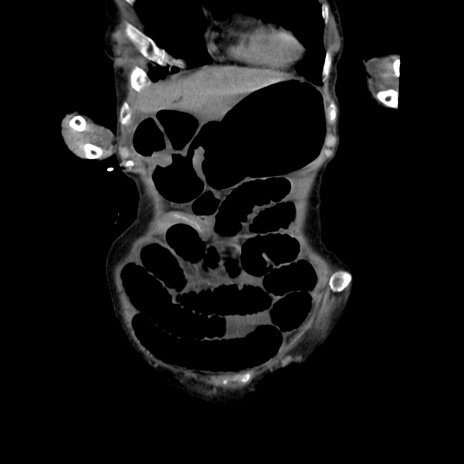

横断像

【症例】80歳代女性

【主訴】嘔吐、腹痛

【現病歴】数時間前より嘔吐あり。心窩部痛出現し、徐々に右下腹痛あり。その後も数回嘔吐あり救急搬送となる。

【既往歴】左大腿骨頚部骨折手術

【身体所見】腹部は膨隆しているが軟らかく圧痛なし。腸雑音はやや亢進。

【データ】WBC 12000、CRP 19.05